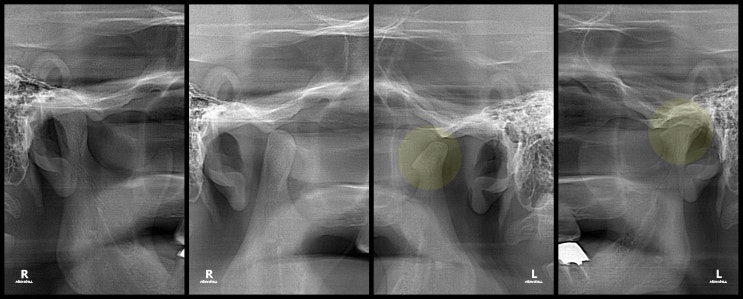

왼쪽 턱에서 자갈 갈리는 소리가 나고, 이가 잘 안 맞물리는 것 같아요.

안녕하세요, 열린구강내과치과 원장 구강내과 전문의 권춘익입니다. 열린구강내과치과가 대구 및 경북에서 ...